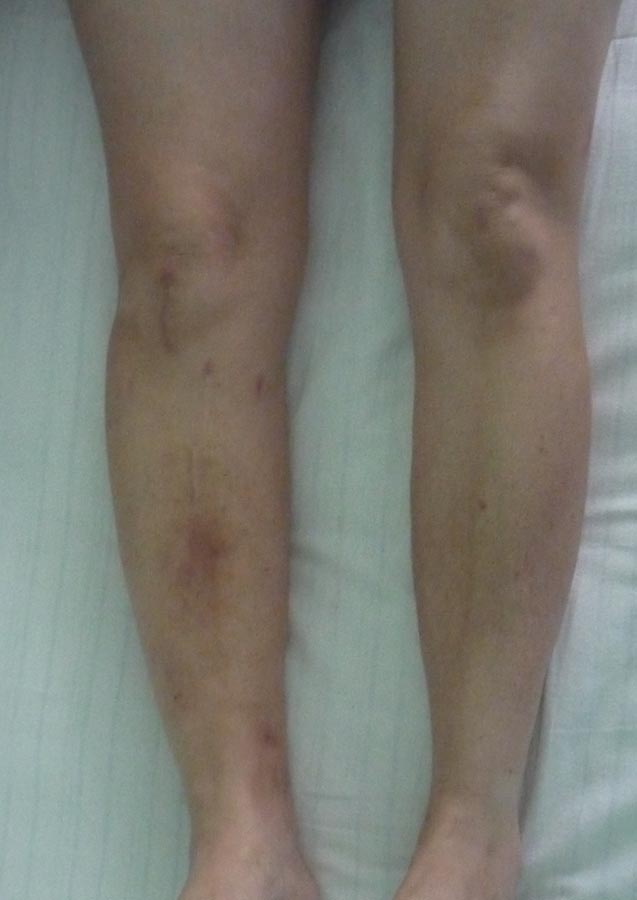

Добрый вечер. Прошу ваше мнения по данному случаю. Поступила Пациентка 50 лет, жительница села. В 18.12.2012 г. в пьяном угаре оступилась о порог двери, после чего поступает в отделение с переломом голени (первоначальных снимков нет). 19.12.2012 г. был выполнен закрытый БИОС, благополучно выписана с рекомендациями. На назначенное время не явилось. Пришла в 26.02.2013 г., тогда удалили 2 блокирующих винта, и в 20.05.2013 г. тоже убрали 2 блокирующих винта. Также благополучно потерялась, появилась в октябре 2014 г., с признаками несращения правой большеберцовой кости. После чего был выполнен реостесинтез штифтом. На данный момент беспокоит боли в области коленного, голеностопного суставов и средней трети голени, отек голени. Как быть дальше????Извиняюсь, 1й БИОС произведен открыто. прилагается фото ноги.